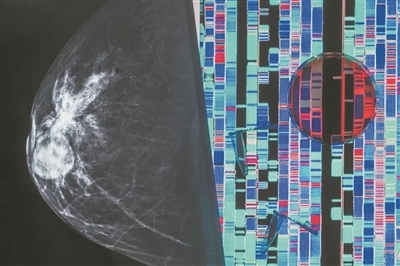

绘制肿瘤及其基因变化图有助于开发新的癌症治疗方法。

图片来源:英国《新科学家》网站

1030日,《自然》及其旗下杂志齐发12篇论文,公布了迄今为止最详细的几种高致死率癌症(胰腺癌、转移性乳腺癌、结肠癌、肾癌、子宫癌和胆管癌)的三维图谱,这为癌症如何形成、发展和对治疗产生耐药性等问题提供了重要线索。